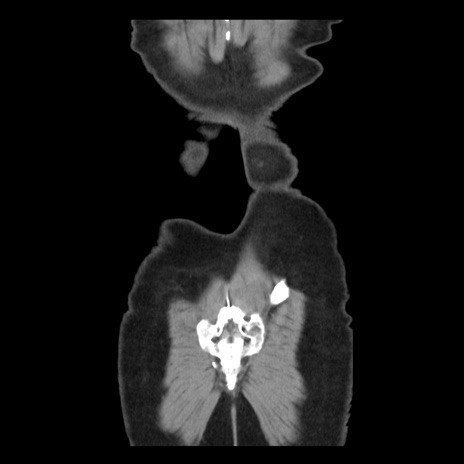

矢状断像

【症例】 50歳代女性

【主訴】 腹痛

【現病歴】前日生レバーを食べた。今朝に排便あり。 昼前に突然発症の腹痛を生じ、当院救急外来を受診した。

【既往歴】 子宮筋腫にてで子宮全摘後

【身体所見】 意識清明、腹部:平坦、軟、下腹部やや左を中心に圧痛・反跳痛あり、筋性防御あり

【データ】WBC 7800、CRP 0.07